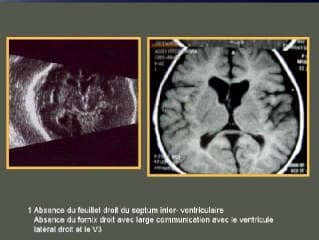

Laurent GUIBAUD nous concocte une formidable boîte à outils à visée diagnostique en 8 points pour une approche systématisée d'une réduction du PC fœtal. Il nous donne comme d'habitude toutes les clés en insistant sur le contexte de survenue qui va orienter l'étiologie comme le CMV ou le zika par exemple. Très didactique donc à s'en imprégner (+++).